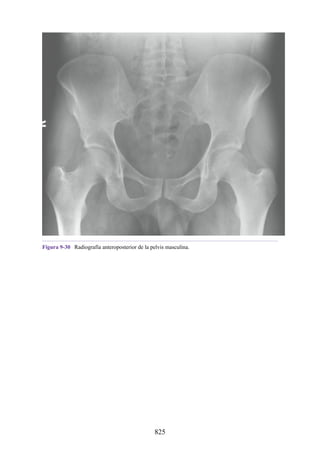

TERRITORIO Inerva todas las áreas del cuerpo. No inerva todas las áreas; la pared

corporal y los miembros carecen de